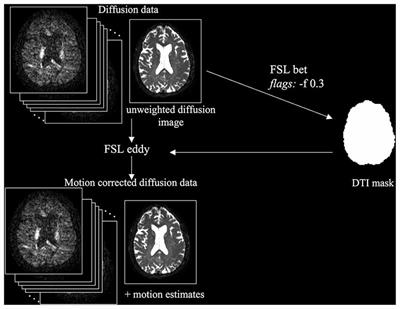

Evaluation of Field Map and Nonlinear Registration Methods for Correction of Susceptibility Artifacts in Diffusion MRI